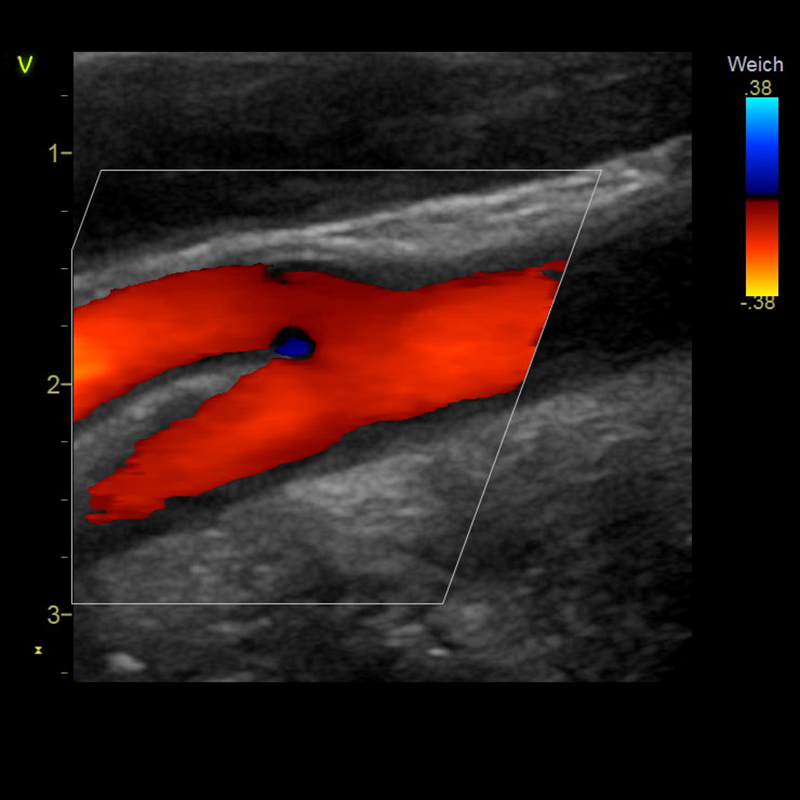

Kardiologie

Seit mehr als 20 Jahren widmen wir uns in unserer Praxis und in der klinischen Forschung der Früherkennung und Behandlung der Herzschwäche.